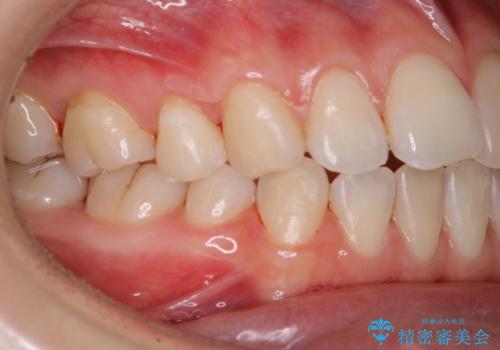

1年ぶりにPMTCで歯の着色落とし

- しばらく歯科医院へ行けなかったため、しっかり着色や汚れを落として欲しいとのことで来院されました。全体的に着色や歯石が付着していたためPMTC60分コースを行いました。

ご自身でのセルフケアだけで着色を落とそうとすると、逆に歯を傷つけてしまったり、的確に汚れを取りきれないことがあります。また、日常生活で着色しやすい飲食物を避けたりすることはストレスに感じてしまったり、あまり現実的ではありません。

定期的に歯科医院にて、適切な処置を行うことで、健康的なお口の状態を維持することにつながります。